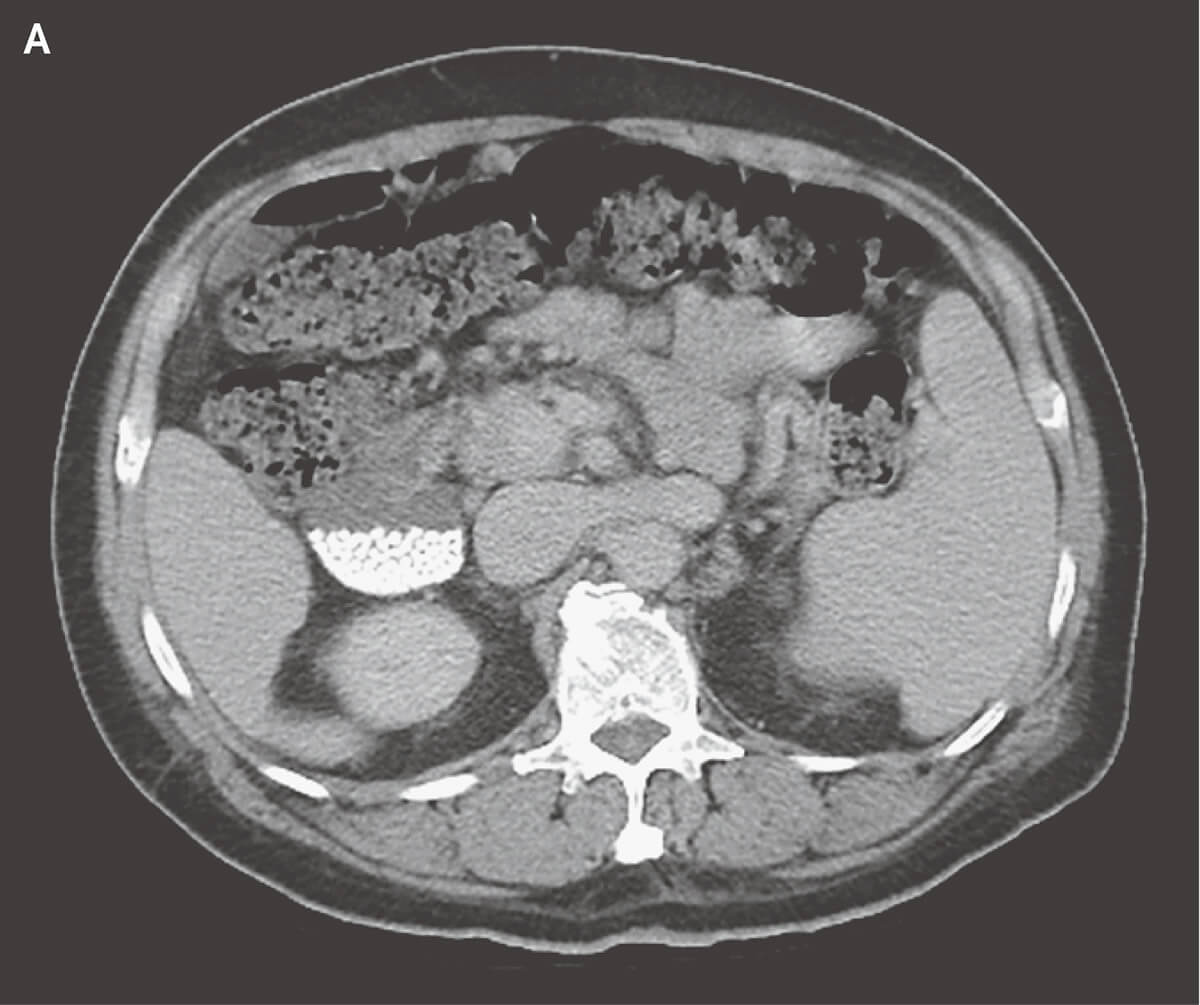

- コンピュータ断層撮影(CT)

- 胆管・胆嚢の結石の有無を構造的に描出する。微小の結石に関しては診断困難なこともある。